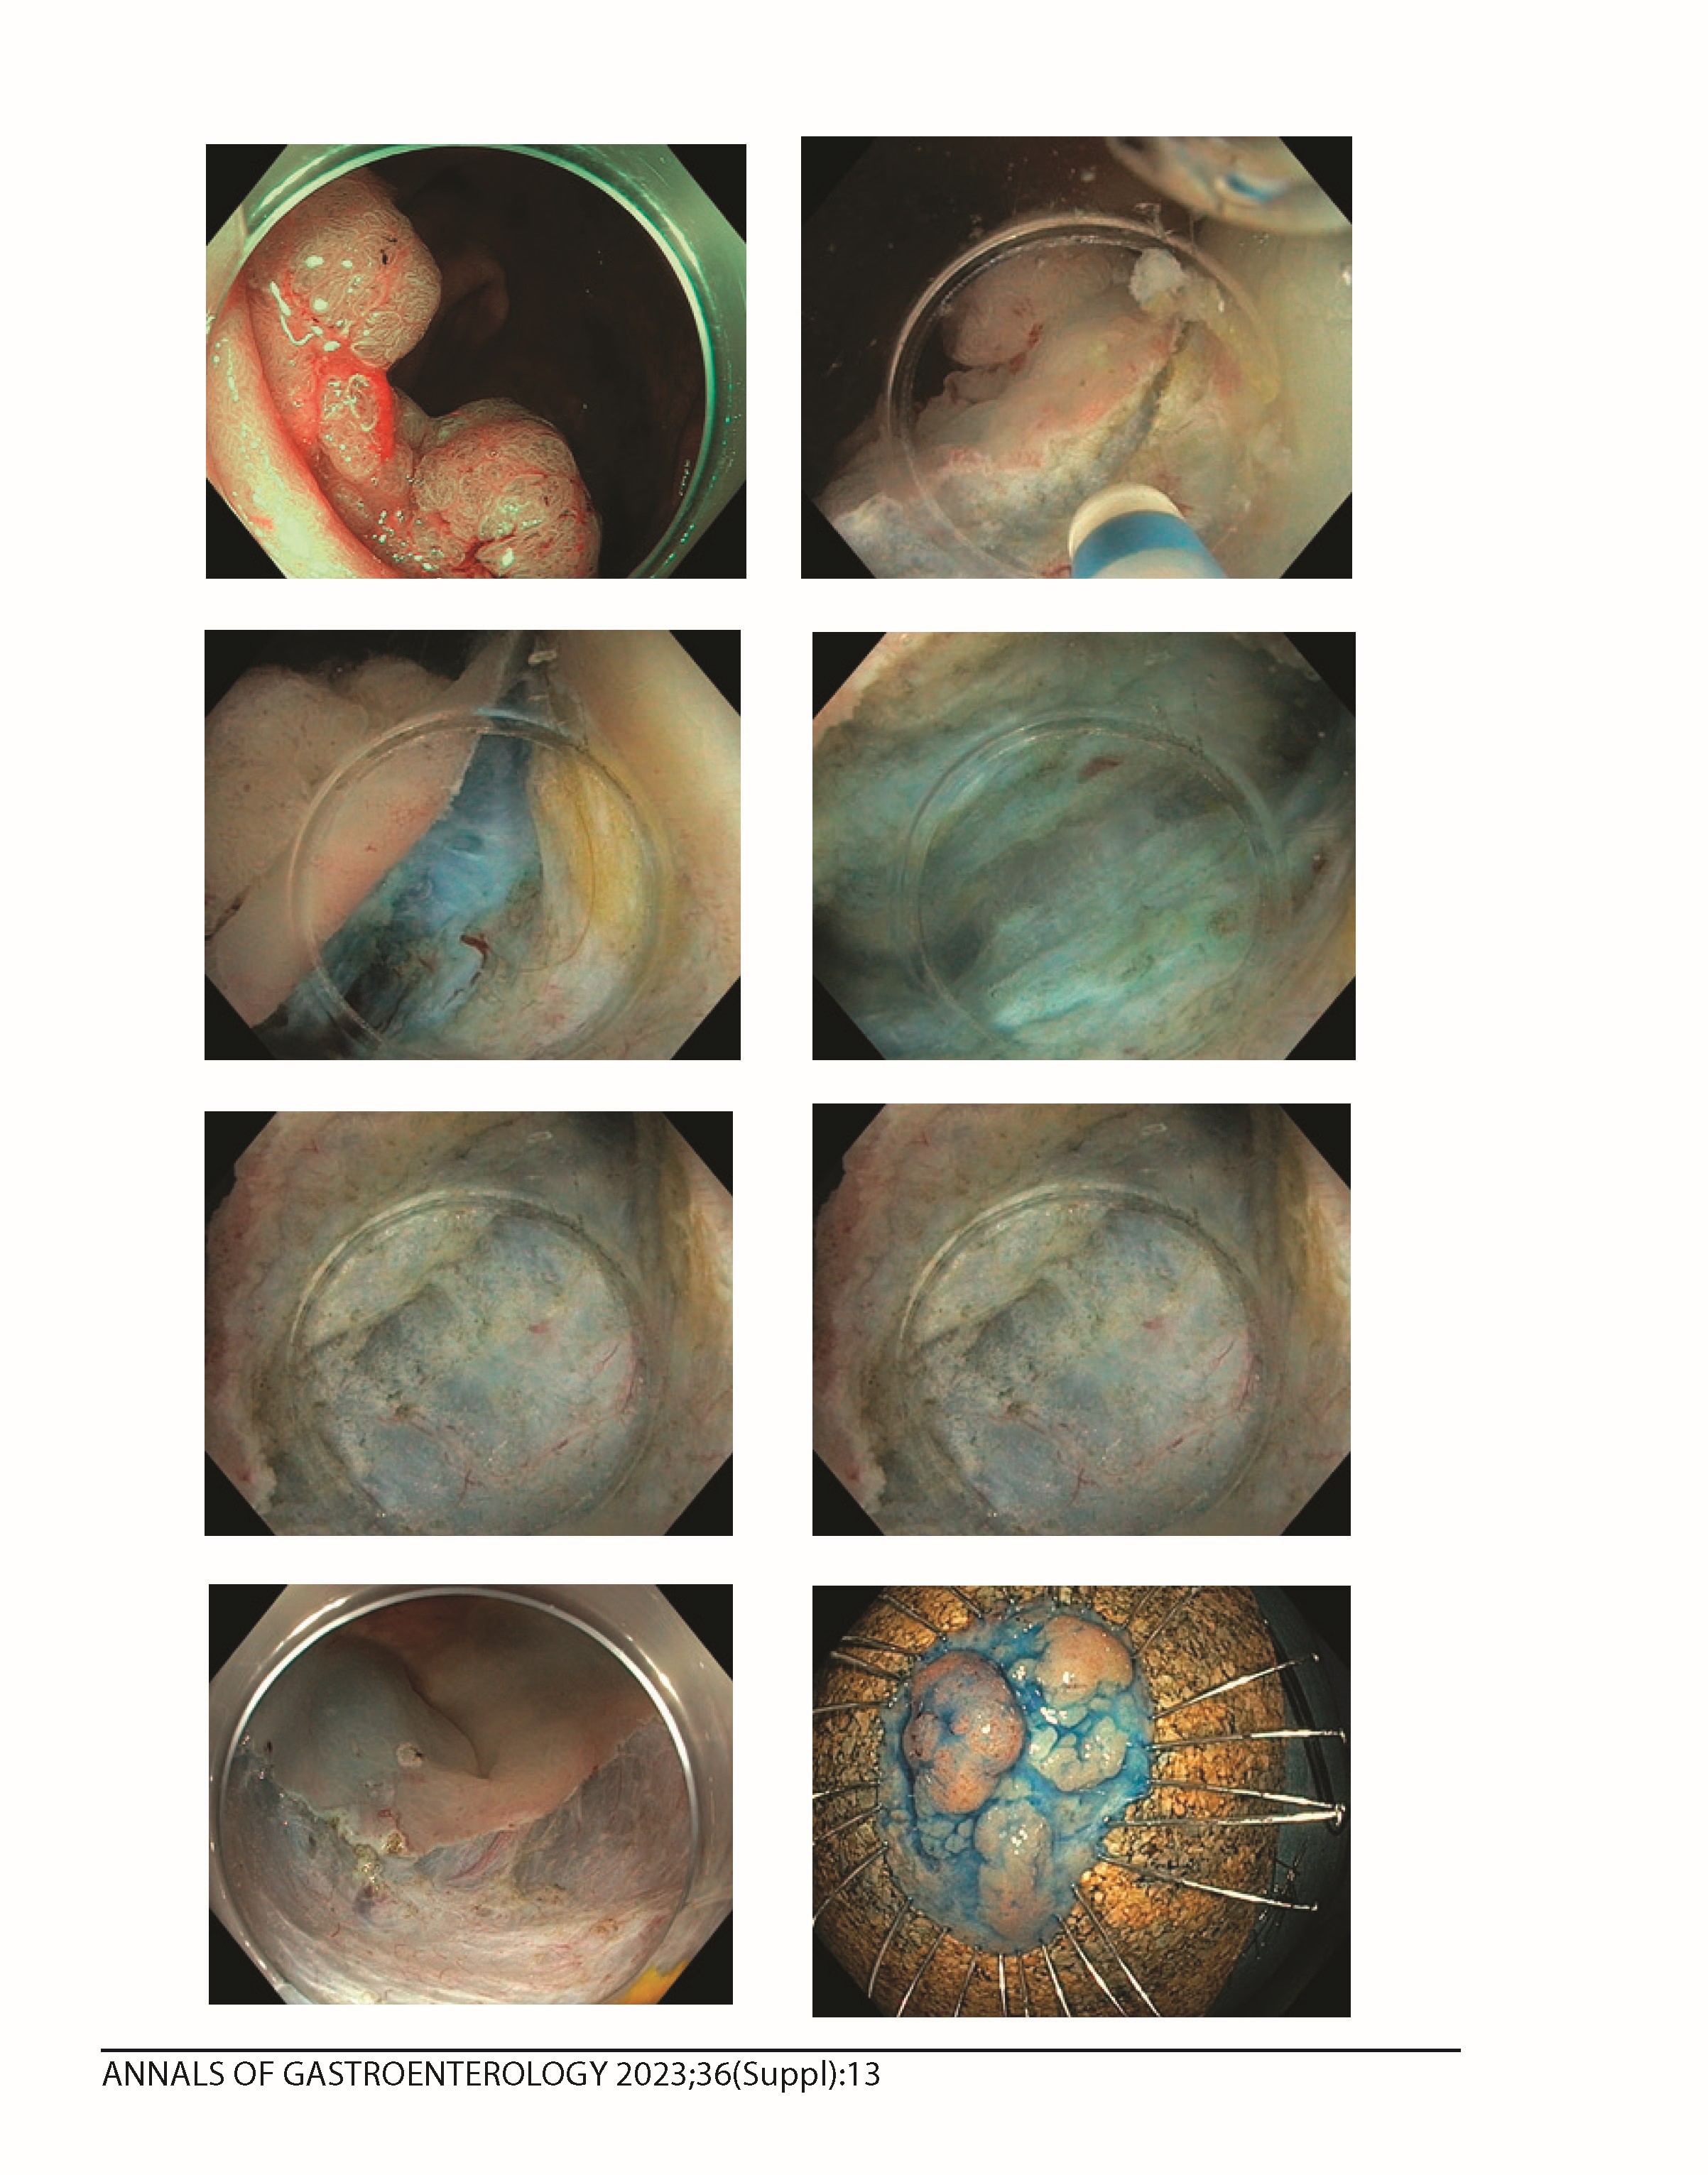

Υποβοηθούμενη με πίεση νερού ενδοσκοπική υποβλεννογόνιος διατομή παχέος εντέρου σε ινωτικές βλάβες

Η εφαρμογή της Ενδοσκοπική Υποβλεννογόνιος Διατομής (ΕSD) σε βλάβες του παχέος εντέρου προϋποθέτει μεγάλη εμπειρία λόγω του κινδύνου διάτρησης του τοιχώματος. Παρά την εξέλιξη τεχνικών αντιέλξης για τη δημιουργία ιδανικού πλάνου διατομής, σε βλάβες με μεγάλη ίνωση η τεχνική δυσκολία παραμένει υψηλή. Η μέθοδος της υποβοηθούμενης με πίεση νερού (water-pressure/WP) ΕSD εφαρμόζεται μέσω έγχυσης φυσιολογικού ορού στο πεδίο της διατομής από την αντλία του ενδοσκοπίου. Η καταβύθιση του ενδοσκοπίου στον ορό δημιουργεί άνωση του βλεννογονικού κρημνού ανεξάρτητα της βαρύτητας, προκαλεί μεγέθυνση 1.33 φορές του πλάνου διατομής και μέσω του φαινομένου της απαγωγής της θερμότητας μειώνει τη θερμική βλάβη στο μυϊκό χιτώνα.